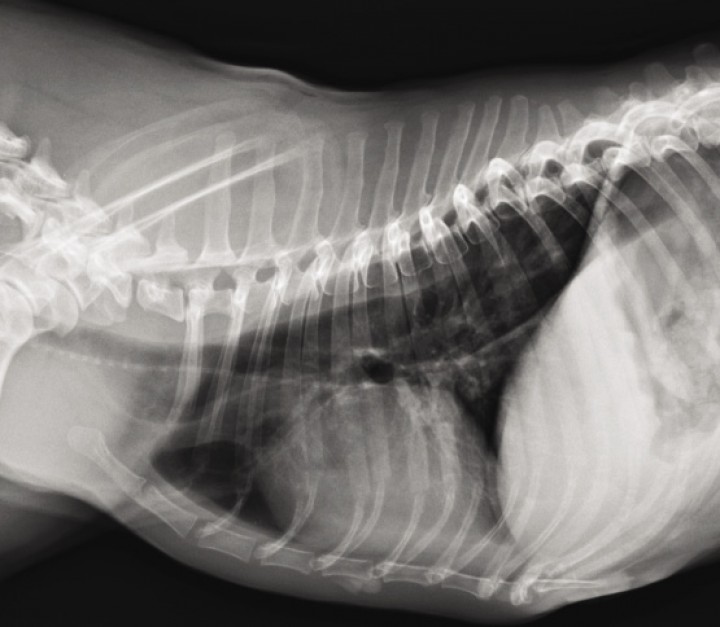

Dos semanas después de la cirugía el animal se presenta de nuevo a la consulta para evaluar los posibles efectos adversos de la quimioterapia y el propietario refiere una historia progresiva de regurgitación. Se realizan radiografías torácicas en proyecciones ventrodorsal y lateral derecha, en las cuales se detecta la presencia de megaesófago (Fig. 8), el cual sería compatible con lesión de las vías nerviosas secundaria a la cirugía.

<p>Radiografía lateral derecha de tórax. Se detecta distensión generalizada de moderada a marcada del esófago intratorácico.</p>

Figura 8

Radiografía lateral derecha de tórax. Se detecta distensión generalizada de moderada a marcada del esófago intratorácico.